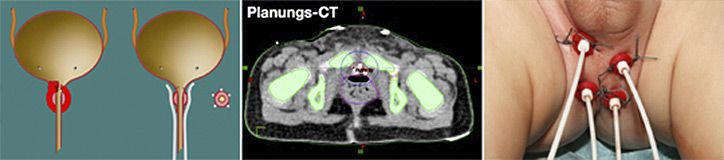

Die Brachytherapie ist eine spezielle Bestrahlungstechnik, bei der die Strahlung über Sonden verabreicht wird. Diese Sonden werden nach der Tumorresektion und nach Rekonstruktion des entsprechenden Organs um das ehemalige Tumorgebiet platziert und nach Ende der Bestrahlung einfach gezogen. Die Bestrahlung findet an mehreren Tagen nach der Tumoroperation statt. Vorteile der Brachytherapie sind eine Fokussierung der Bestrahlung auf das tatsächliche Tumorgebiet und die Schonung des umgebenden, gesunden Gewebes.

Eine organerhaltende Tumorresektion mit anschließender Brachytherapie kann bei Kindern mit Rhabdomyosarkom der Prostata, der Harnblase, der Vagina und perianalen Rhabdomyosarkomen durchgeführt werden. In den letzten 10 Jahren haben wir über 40 Kinder mit einem Blasen/Prostata-Rhabdomyosarkom organerhaltend operiert. Bei 26 dieser Kinder haben wir erfolgreich die Kombinationstherapie mit einer Brachytherapie durchgeführt.